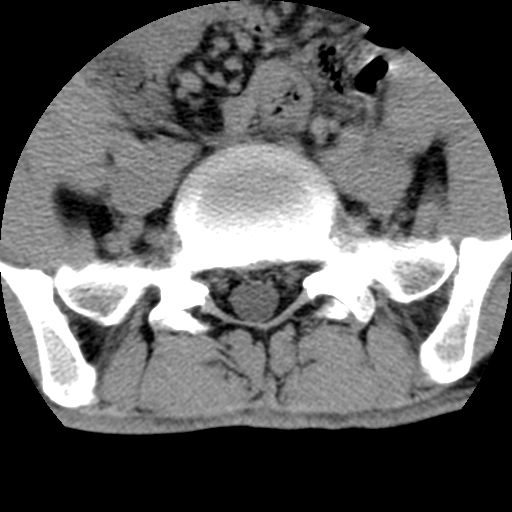

标题: CT16890:男,腰背痛.

男,腰背痛

本人诊断1tb2包虫,请会诊

1)右侧竖脊肌稍低密度肿块伴钙化(性质待定),不排除肿瘤可能;建议行进一步检查。2)腰椎间盘突出。

1.右侧竖脊肌软组织肿块伴团块状钙化,首先考虑血管瘤可能性大;建议行进一步检查;2。腰椎间盘突出。